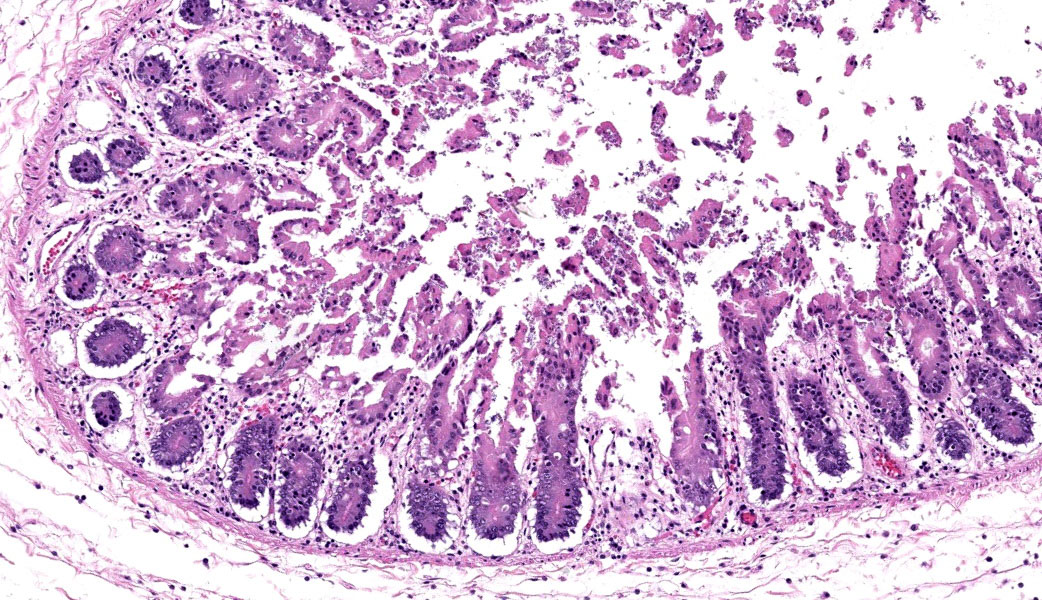

Cecum at ileocecocolic junction: One full-thickness cross sections of cecum at the ileocecocolic junction are examined from each animal (2 total). Diffusely, the submucosa is expanded by clear space (edema) and admixed inflammatory cells (neutrophils, macrophages, lymphocytes, and fewer plasma cells). The lamina propria is multifocally expanded by edema, hemorrhage, the previously mentioned admixed inflammatory cells, and karyorrhectic debris. The overlying epithelium has multifocal erosions and ulcerations with surface necrotic debris and mixed bacterial colonies.

Colon: Colitis, necrotizing, subacute, multifocal, moderate, with volcano lesions, hemorrhage, and severe submucosal edema.

Similar to Case 1, due to the presence of volcano lesions coupled with mucosal ulceration/necrosis and heterophilic inflammation, Dr. Uzal says this is C. difficile until proven otherwise! This case had some solid examples of volcano lesions in which heterophils could be seen exploding out of tiny ulcers in the mucosa.

Histologically, the colon was severely edematous and had gram-positive bacilli present within areas of mucosal necrosis that showed up beautifully on a Gram stain performed by Dr. Uzal’s lab. A secondary bacterial infection was considered by conference participants in the markedly dilated sections of gut in this case, especially since rabbits frequently have multispecies enteric infections similar to cattle (i.e. coronavirus, rotavirus, C. difficile, E. coli, etc.), but there was no laboratory testing available to confirm this. C. difficile, however, was confirmed by the contributor via ELISA for A/B toxin.